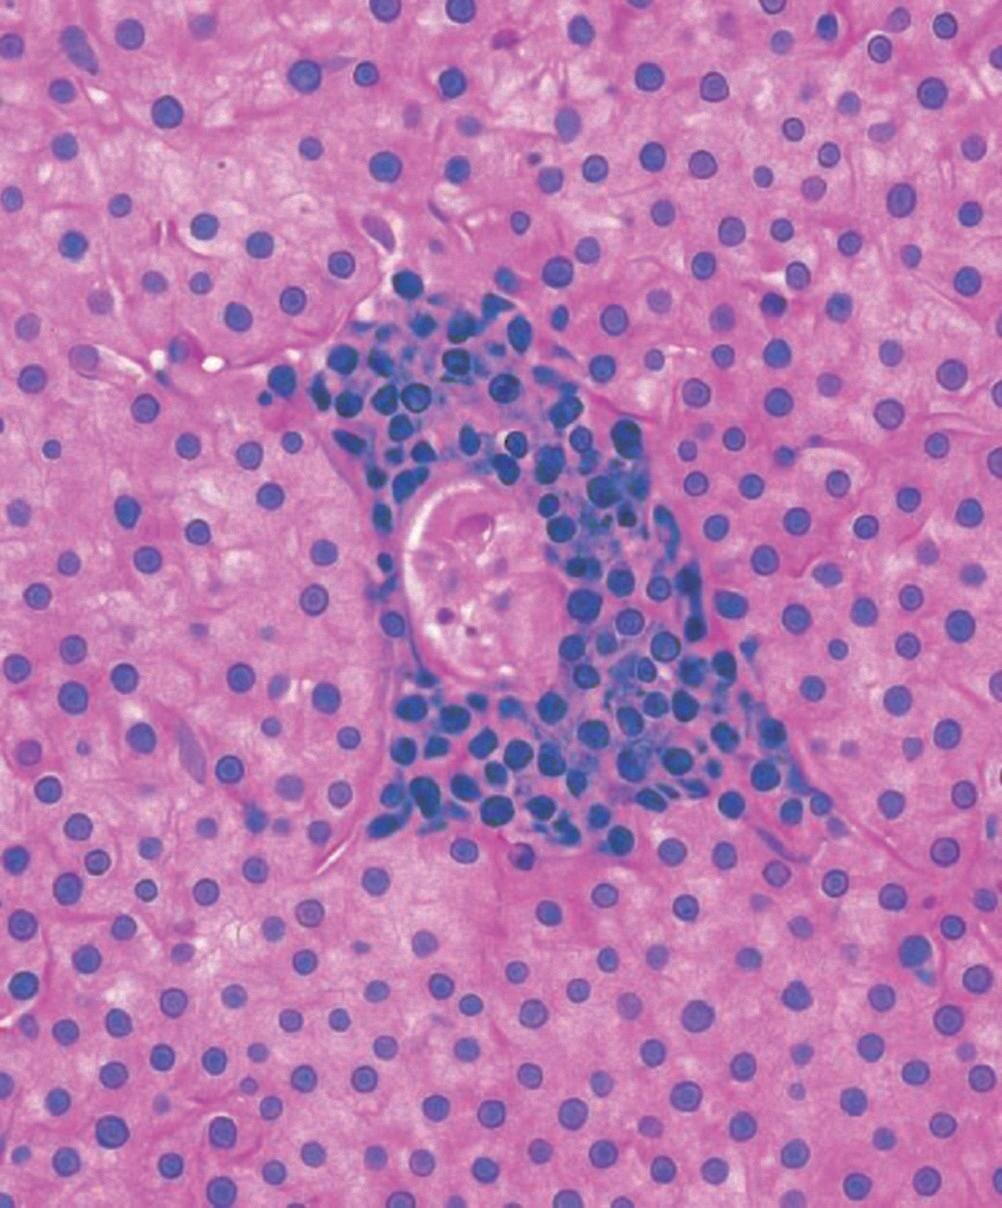

Paciente do sexo masculino, 34 anos de idade, procura o serviço de emergência com queixa de icterícia progressiva há 2 semanas, associada à fadiga intensa, ao prurido cutâneo e à febre baixa intermitente. Relata perda de peso não intencional de 8kg nos últimos 3 meses, além de diarreia crônica e sudorese noturna. Negou uso de álcool, drogas ilícitas ou medicamentos hepatotóxicos. Não possui histórico prévio de doenças hepáticas ou transfusões sanguíneas. Durante a anamnese, o paciente mencionou comportamento sexual de risco, com múltiplos parceiros sem uso regular de preservativo. Estado geral: regular, emagrecido, consciente e orientado. Pele e mucosas: icterícia acentuada, sem lesões cutâneas. Abdome: fígado palpável a 3cm do rebordo costal direito, doloroso à palpação. Baço palpável a 2cm do rebordo costal esquerdo. Sem ascite. Outros achados: linfonodomegalia cervical e inguinal bilateral. Exames complementares: hemograma: leucopenia (2.800/mm³), linfopenia absoluta (500 células/mm³), plaquetas normais. Alanina aminotransferase (ALT): 85U/L (valor de referência [VR]: 7 a 55); aspartato aminotransferase (AST): 92U/L (VN: 8 a 48); gamaglutamiltransferase (GGT): 580U/L (VN: 9 a 48); fosfatase alcalina (FA): 420U/L (VN: 40 a 129); bilirrubina total: 8,5mg/dL (VN: 0,2 a 1,2); índice internacional normalizado (INR; do inglês, international normalized ratio): 1,5 (VN: 0,8 a 1,2).

(anti-HBS) >150 (reagente). Citomegalovírus (CMV), herpes simples e vírus Epstein-Barr imunoglobulina M (IgM) não reagentes. Teste para vírus da imunodeficiência adquirida (HIV): positivo. Carga viral do vírus da imunodeficiência humana (HIV): 250.000 cópias/mL. CD4+: 80 células/mm³ (grave imunossupressão).

Ultrassonografia (USG) abdominal com hepatomegalia e esplenomegalia, sem evidência de obstrução biliar. Ressonância magnética (RM) de abdome com colangiopancreatografia por ressonância magnética (CPRM) sem alterações dos ductos biliares intra- ou extra-hepáticos.

1. Qual é a hipótese diagnóstica mais provável para a colestase intra-hepática do paciente descrito no caso clínico?

A. Colangite associada à síndrome da imunodeficiência adquirida (Aids) por infecção oportunista

B. Colangite esclerosante primária (CEP)

C. Hepatite viral aguda por vírus da hepatite B (HBV)

D. Toxicidade hepática por uso de antirretrovirais

2. Considerando a hipótese diagnóstica para o caso clínico, qual seria a estratégia ideal para concluir o diagnóstico e iniciar o tratamento adequado?

A. Iniciar terapia antirretroviral (TARV) imediatamente e aguardar melhora clínica

A. Fibrose perisinusoidal isolada

B. Granulomas caseosos com necrose central

C. Granulomas não caseosos periportais

D. Infiltrado neutrofílico em ductos biliares